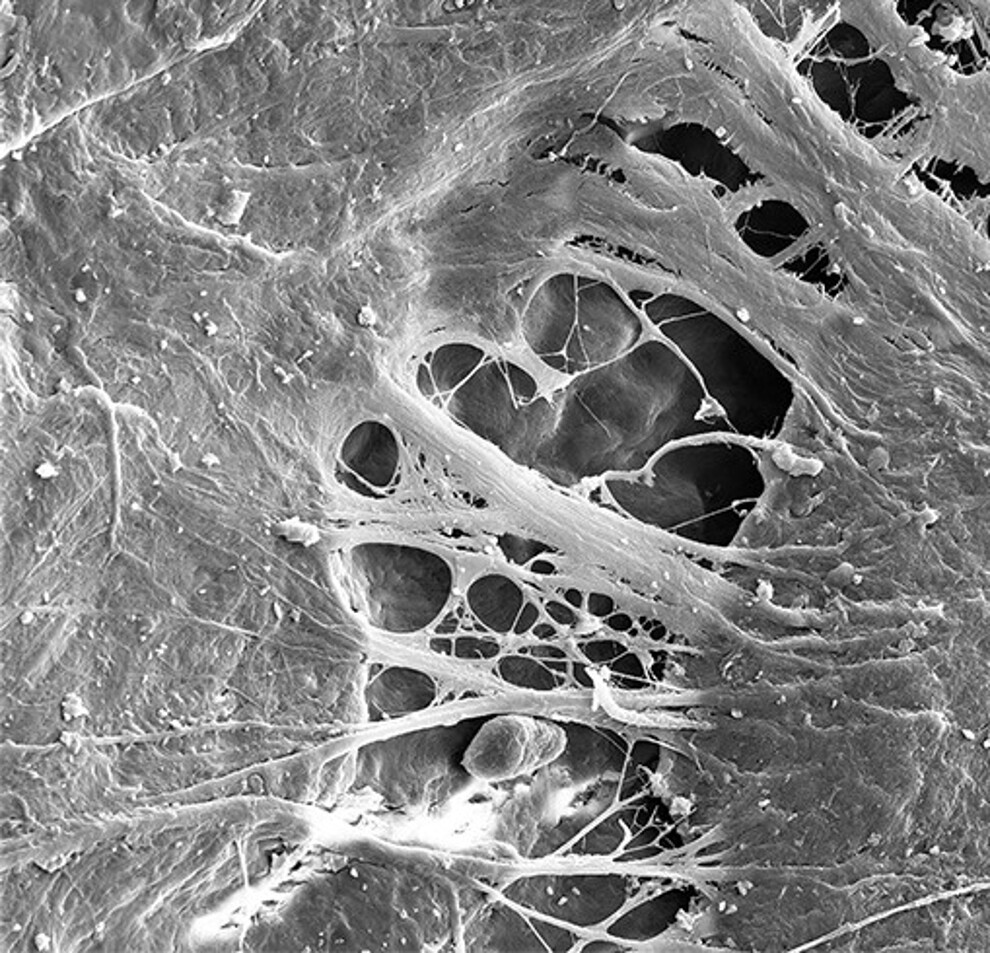

Fig. 1 : Micrographie électronique à balayage illustrant l’interface entre Patent Symbionic Teeth et les tissus mous environnants, mettant en évidence l’intégration et la continuité structurale au niveau de la jonction tissulaire. (Photo : Dr Roland Glauser)

Avec Patent Symbionic Teeth, la reconstitution d’une telle barrière devient possible pour la première fois. Patent Symbionic Teeth sont la première solution de remplacement dentaire capable de reconstituer une barrière muqueuse, offrant une protection des tissus comparable à celle observée autour des dents naturelles. Cette innovation marque une évolution logique des implants conventionnels, en intégrant une dimension biologique jusqu’ici insuffisamment reproduite. Seules Patent Symbionic Teeth ont permis de démontrer scientifiquement, pour la première fois, ce processus biologique inédit (Fig. 1).